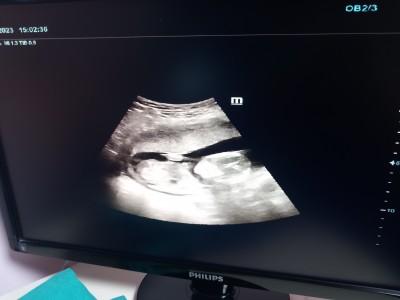

12 haftalıkken doktor erkek dedi özelde sonra 15 haftalıkken devlete  gittim bacakları kapalı kız olabilir dedi  16+5 özele gittim erkeğe benziyor dedi çok merak ediyorum ya

Bişey görmedim ben daha net yok mu kesesi falan belli olan bı fotoğraf

Zaten görünen yer bacak arası